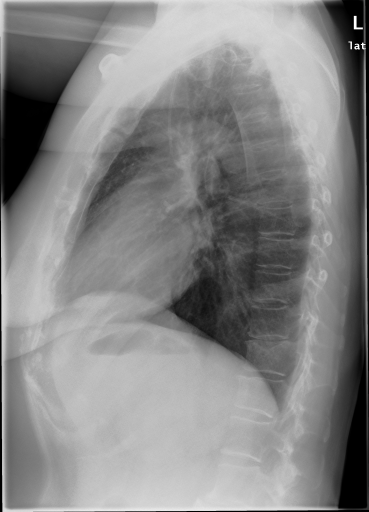

Details of the IRMA database is described in literature [24],[27],[25]. IRMA dataset offers 12,677 images for training and 1,733 images for testing. Figure 4 shows some sample images from the dataset long with their IRMA code in the format TTTT-DDD-AAA-BBB.